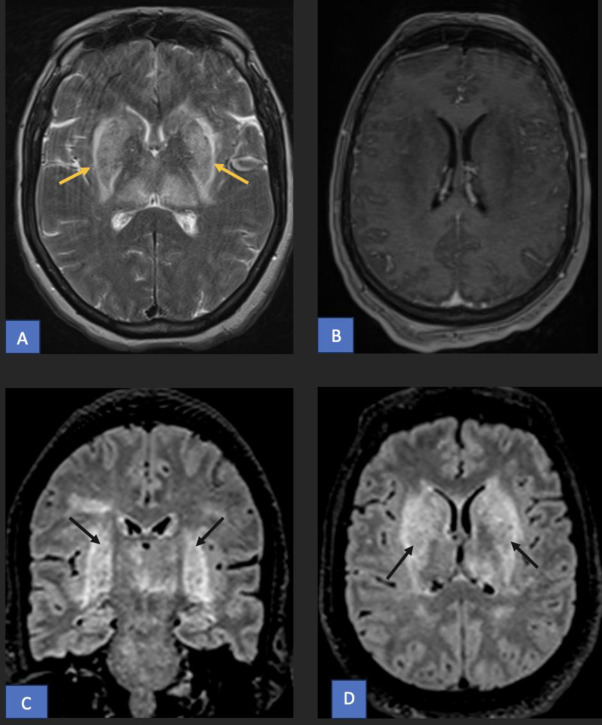

💡Lentiform fork sign on MRI typically points to uremic encephalopathy… but not always. ✅Normal renal function should raise suspicion. In this case, CSF revealed anti-NMDA receptor antibodies → autoimmune encephalitis. doi.org/10.1016/j.radc…

👱♀️58F with 2 weeks of confusion, behavioral change, and seizures. Labs unremarkable, renal function normal. 🍴On MRI I see… a fork? 👀What do you see?